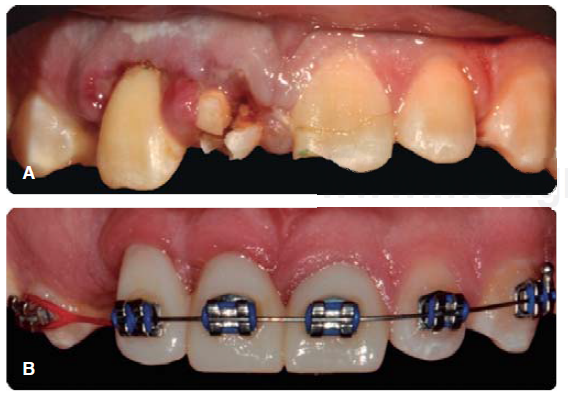

Control periodontal durante el inicio del tratamiento de ortodoncia

El paciente fue citado para realizar el control personal de placa y darle indicaciones de cepillado con la actual aparatología ortodóntica (Figura 14).

Durante esta cita de control periodontal, se realizan radiografías dentoalveolares, en las que se observa una resorción radicular, la cual se puede atribuir a una respuesta inflamatoria del ligamento periodontal como respuesta al traumatismo o a los movimientos ortodónticos (Figura 15).